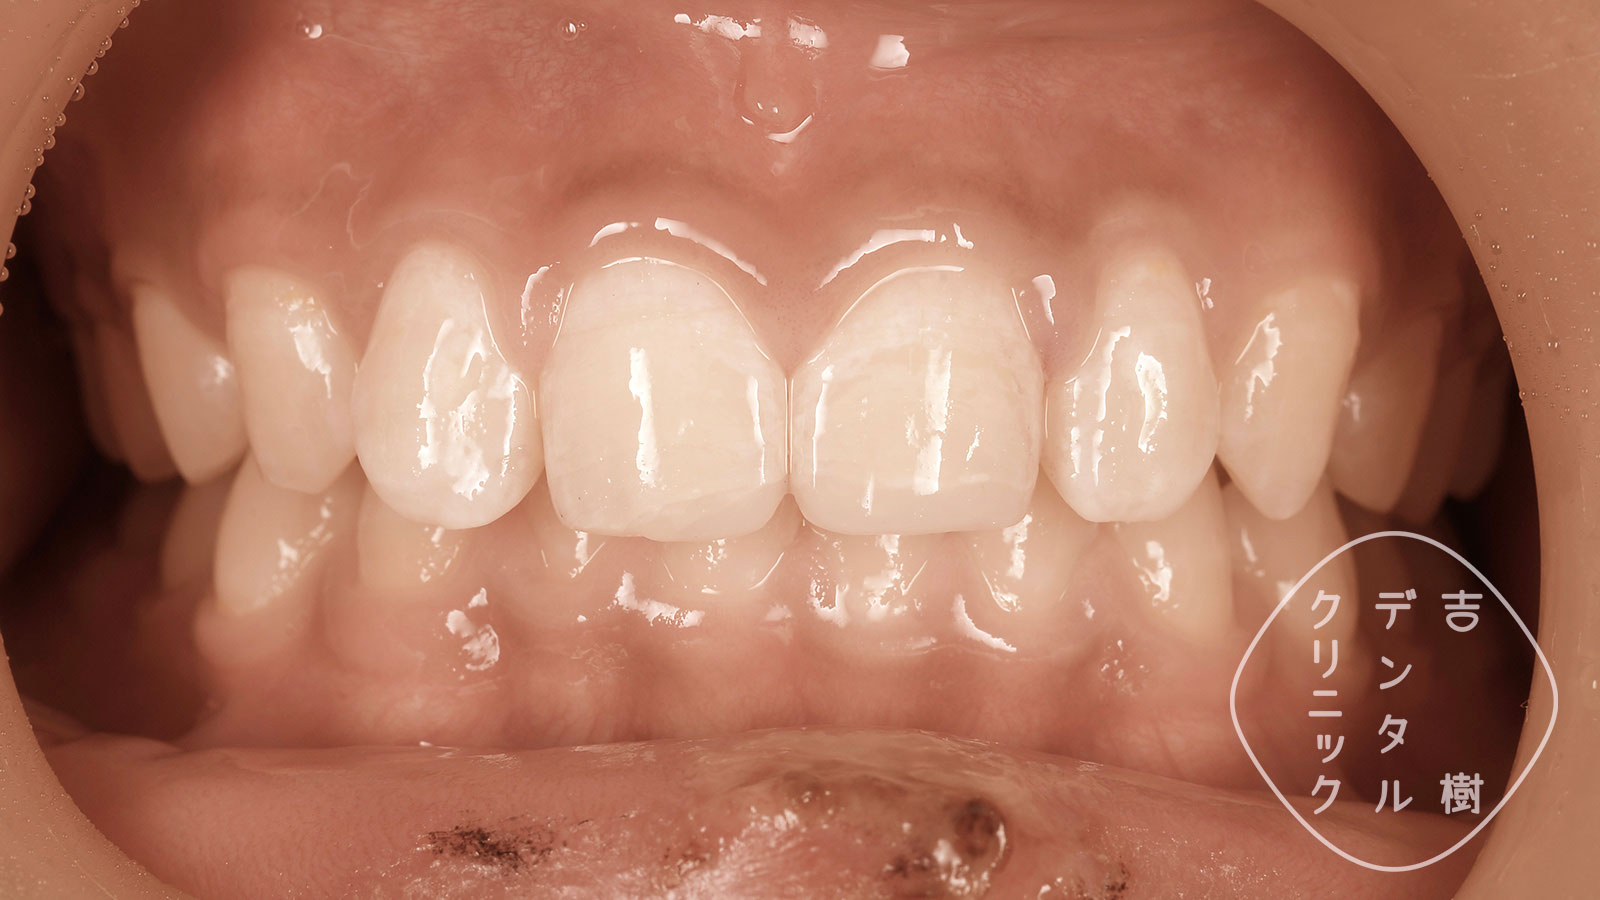

当院では、「ダイレクトボンディング」という治療法で、歯冠破折を修復できます。歯が折れた当日に修復することも可能です。

破折の当日にダイレクトボンディングで修復したケース。